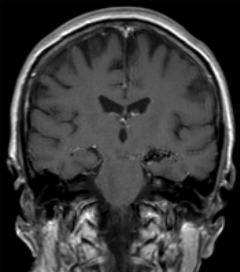

Arteriovenous malformations, or AVMs, occur when an abnormal connection forms between arteries and veins, making a tangle of vessels. AVMs can be found anywhere in the body, but brain and spinal AVMs are especially dangerous when they bleed. If you have an AVM, among other symptoms, you can expect to experience headaches and/or seizures. AVMs are often found when patients have a brain or spine scan for other health issues or the vessels rupture.

AVM treatment can vary from patient to patient. In some cases the AVM can be removed surgically. If an AVM is too difficult to reach, radiation may be used to eliminate it. This procedure is called sterotactic radiosurgery. Doctors find the location of the AVM with a cerebral angiogram and send high-energy beams to destroy the AVM. Some AVMS don’t require treatment at all, and can be monitored.